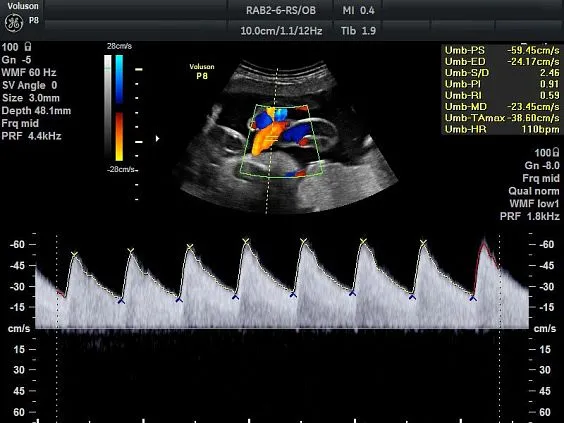

Клинические изображения

Voluson P8 одинаково уверенно справляется как с задачами в сфере женского здоровья (оценка развития плода, диагностика патологий малого таза), так и при сканировании сердца, сосудов, органов брюшной полости и поверхностных структур. Аппарат поддерживает современные технологии обработки изображения: HD-Flow™, Speckle Reduction Imaging (SRI), CrossXBeam™, что позволяет получить максимально чёткие и информативные данные даже в сложных клинических условиях.

- RAB2-6-RS - датчик 4D конвексный 2-5 МГц для акушерско-гинекологических и абдоминальных исследований. Имеет уменьшенные эргономичные габариты и вес

- Усовершенствованное цветовое допплеровское картирование — для более детального исследования анатомии и функционального состояния сосудистой системы.

- Автоматическая оптимизация в 2D и допплеровском картировании в одно касание позволяет улучшить контрастное разрешение и облегчить исследование в режиме спектрального допплера.